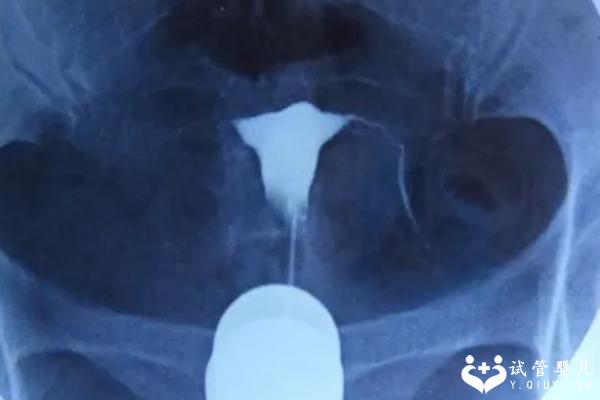

目前还没有方法可以通过手术缩短输卵管长度来提高试管受孕成功率。传统的治疗方法通常是进行输卵管造影检查,并根据检查结果确定是否需要切除或修复输卵管。但是这种方法并不能解决输卵管过长的问题,只能帮助我们找到更好的治疗方案。